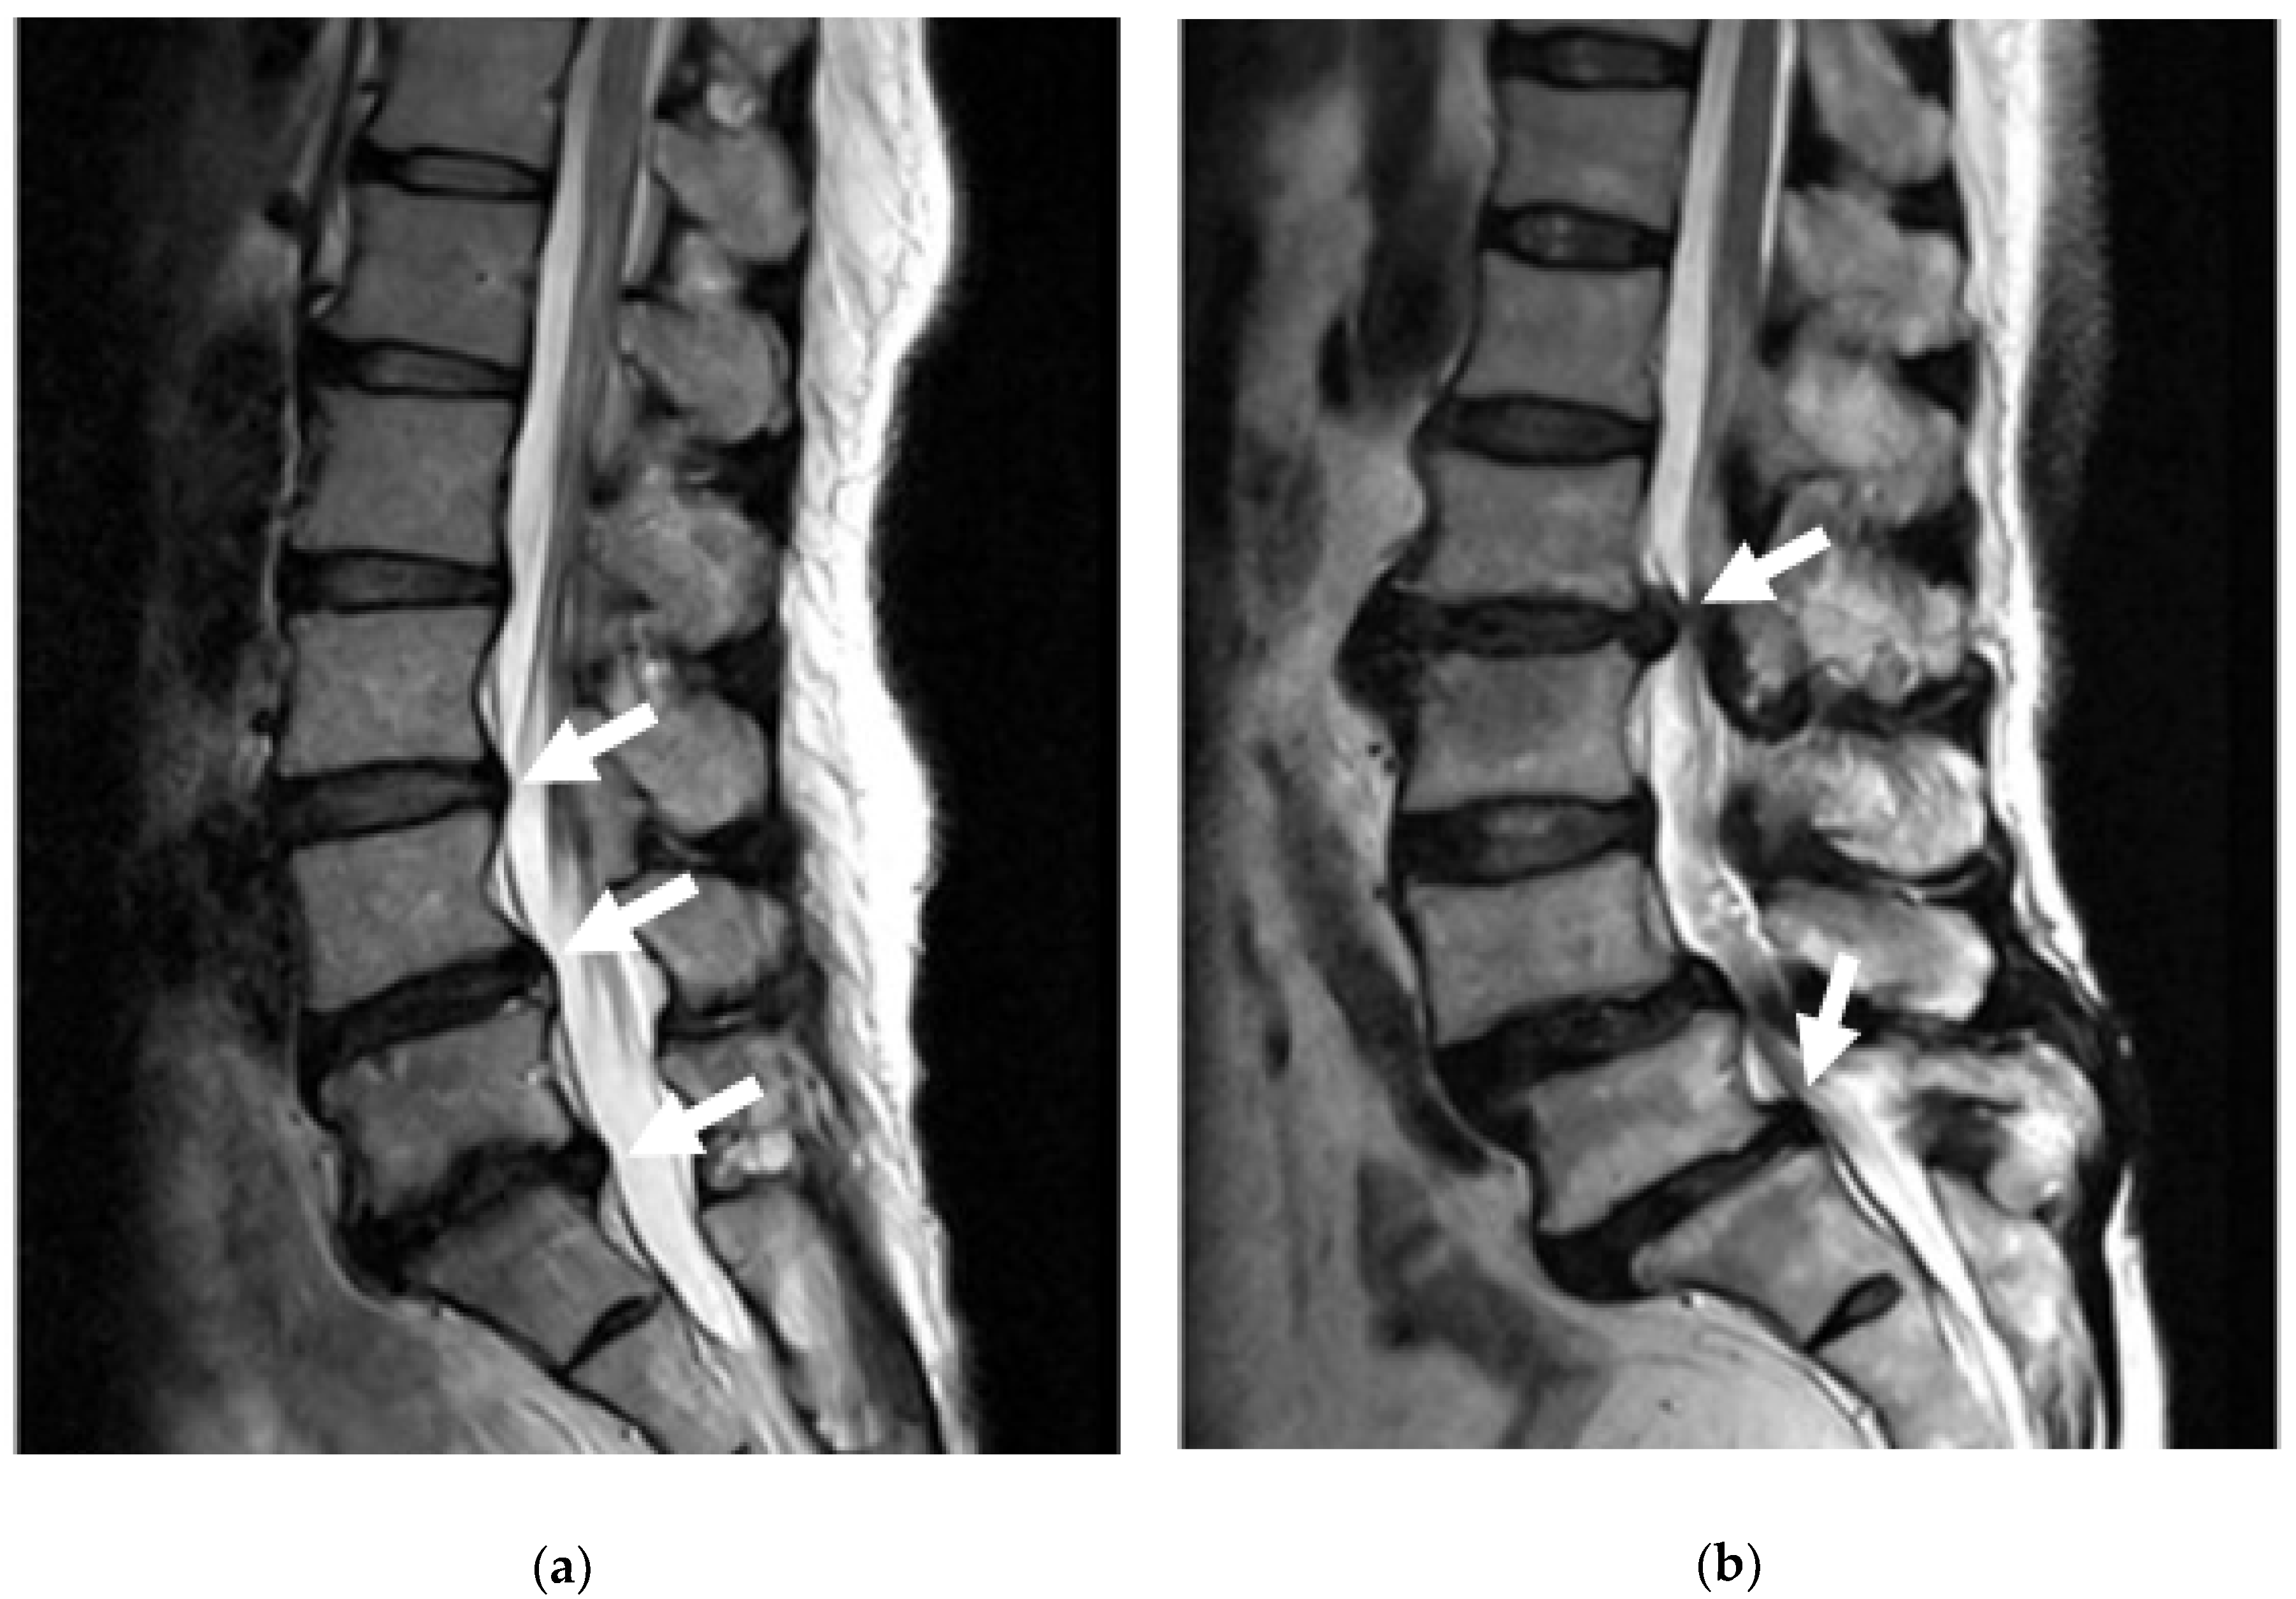

3.4. Disc Herniation (Prolapse/Rupture)

- Pfirrmann, C.W.A.; Metzdorf, A.; Zanetti, M.; Hodler, J.; Boos, N. Magnetic Resonance Classification of Lumbar Intervertebral Disc Degeneration. Spine 2001, 26, 1873–1878. [Google Scholar] [CrossRef]

- Radek, M.; Pacholczyk-Sienicka, B.; Jankowski, S.; Albrecht, L.; Grodzka, M.; Depta, A.; Radek, A. Assessing the correlation between the degree of disc degeneration on the Pfirrmann scale and the metabolites identified in HR-MAS NMR spectroscopy. Magn. Reson. Imaging 2016, 34, 376–380. [Google Scholar] [CrossRef]